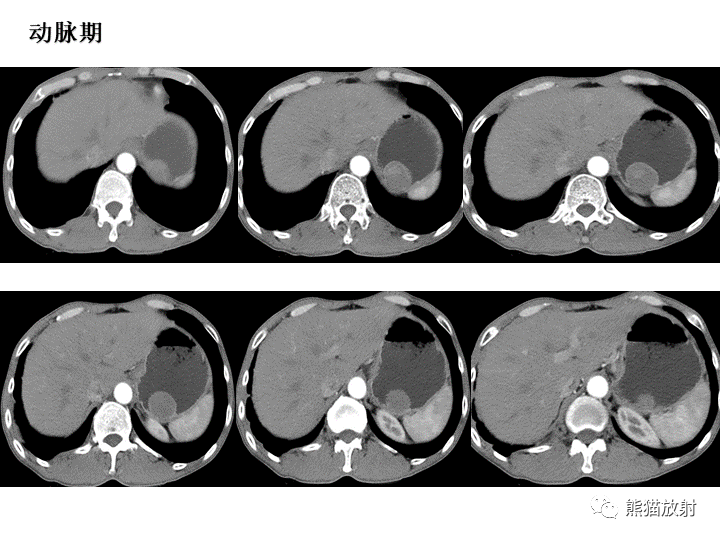

【病例】胃间质瘤VS神经鞘瘤-2